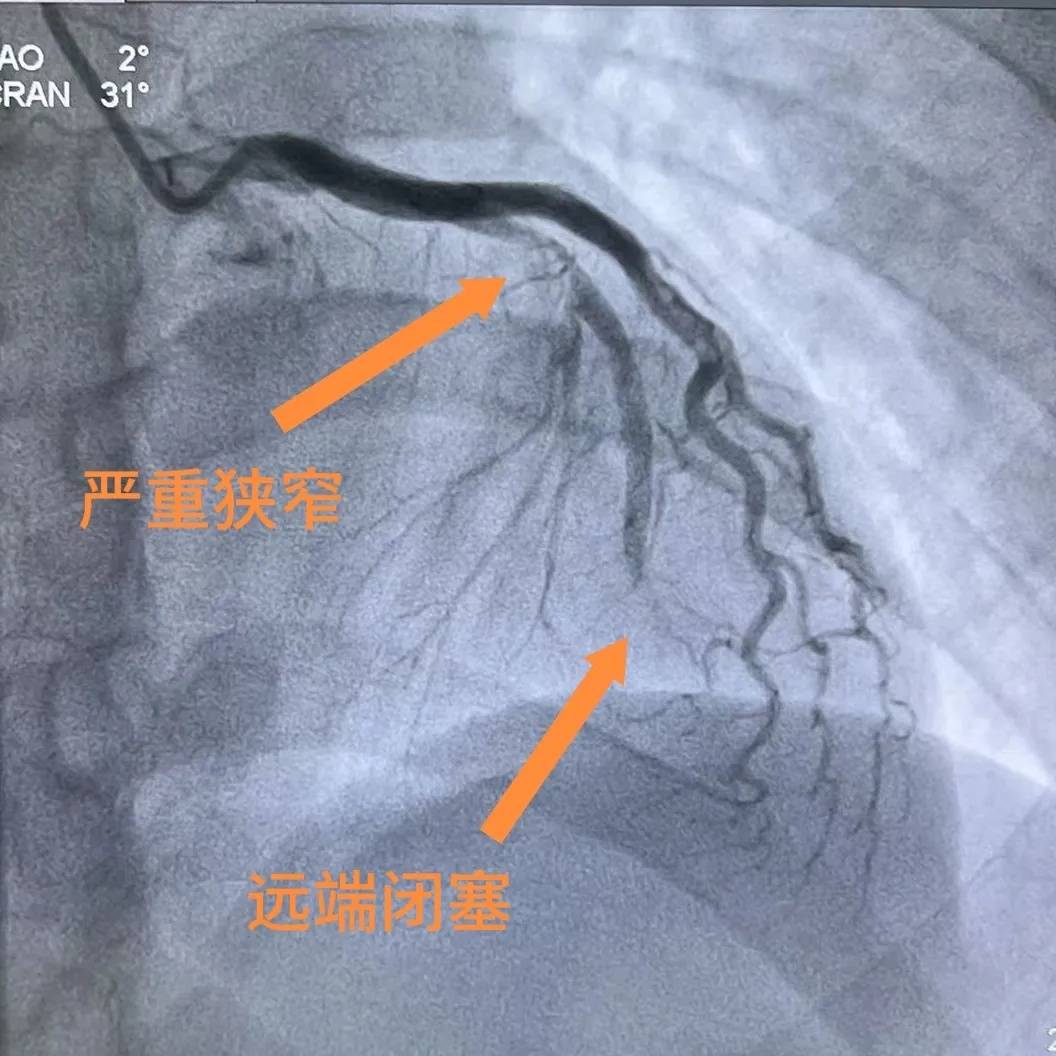

术前造影

玉环二医胸痛中心立即启动绿色通道,林先生急诊冠脉造影结果令人惊心:心脏供血的关键血管——左前降支近中段狭窄高达90%,远端已完全闭塞,血管内堵塞着大量血栓,随时可能引发心脏骤停,危及生命。